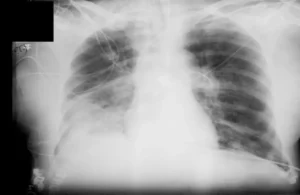

وتقول: “الأشعة السينية هي إشعاع كهرومغناطيسي، مثل الأشعة فوق البنفسجية والضوء والحرارة. صحيح قد تلحق جرعاتها العالية الضرر بالخلايا، كالذي تسببه حروق الشمس. وأن الاستلقاء تحت أشعة الشمس على الشاطئ دون حماية أخطر بكثير من تصوير بالأشعة السينية للصدر مرة واحدة سنويا”.

وتؤكد بلاتونوفا، أن عدم اكتشاف المرض أخطر بكثير من الخضوع للأشعة السينية، حيث المعدات الحديثة تقلل من المخاطر، كما أن الفحوصات في الوقت المناسب تسمح بالكشف السريع عن الأمراض وبدء العلاج.